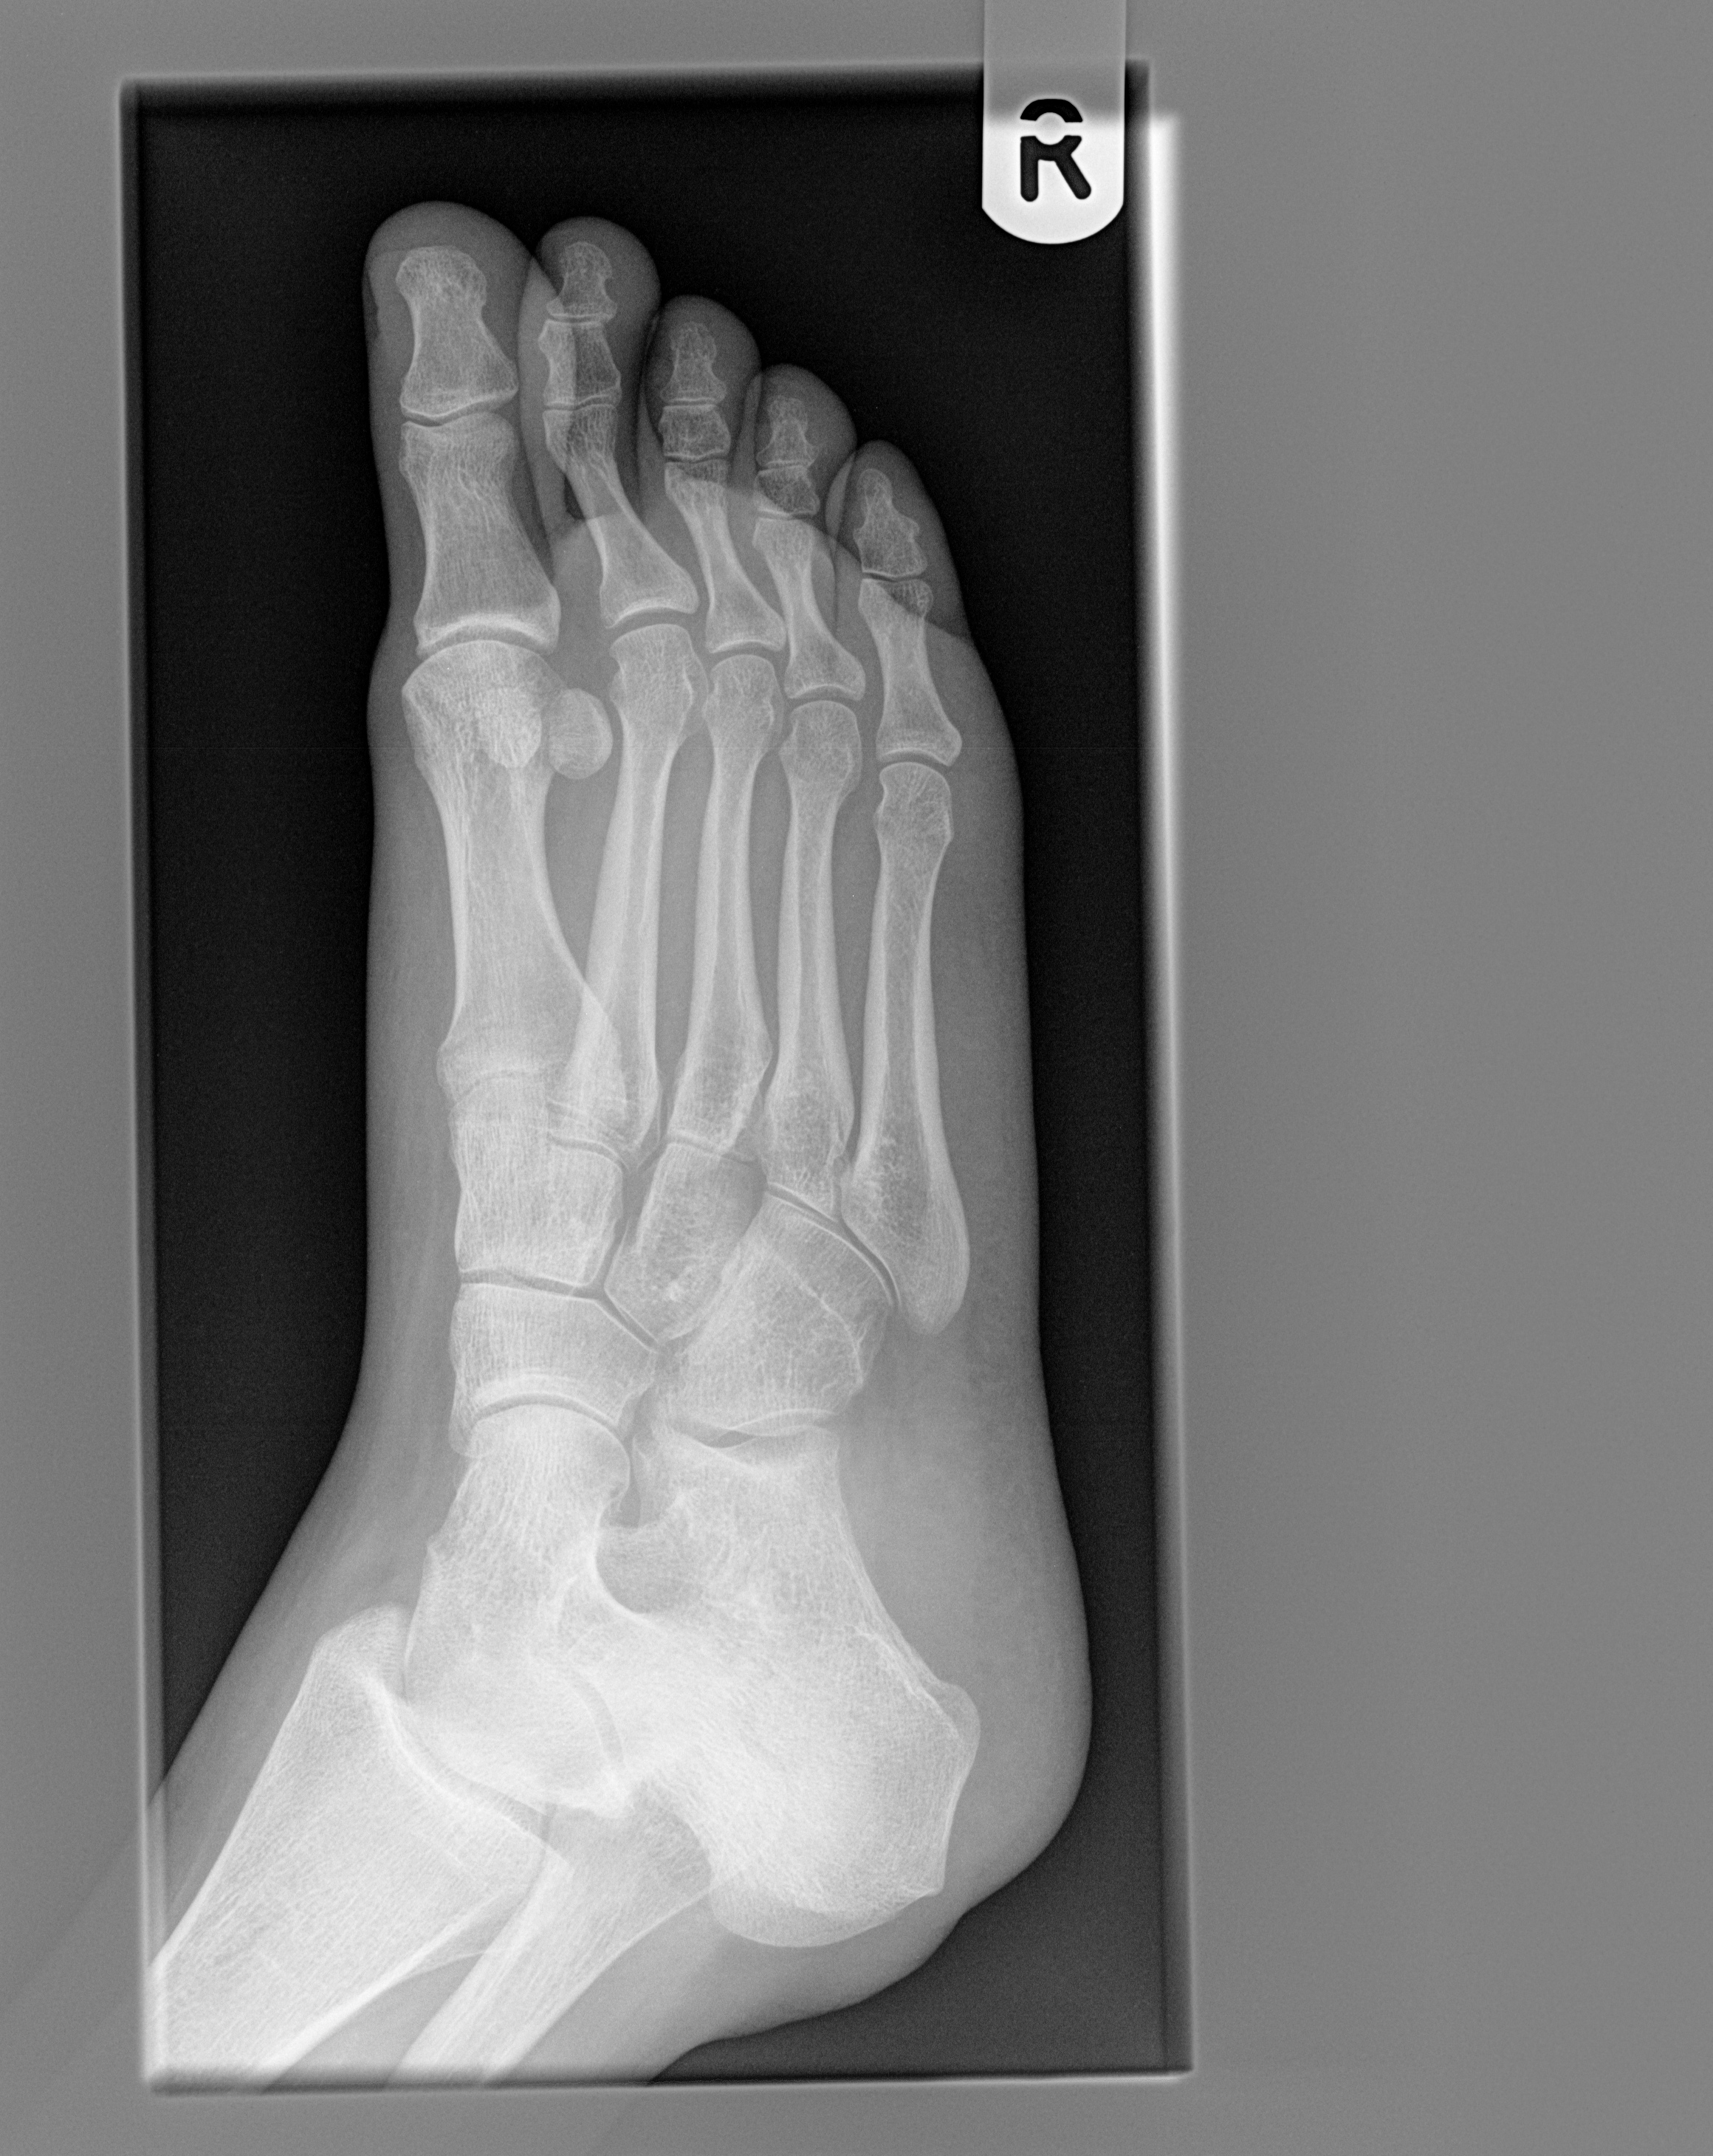

A distal radius fracture is a common bone fracture of the radius in the forearm. To code a diagnosis of this type, you must use specify a 7th character that describes the diagnosis 'colles' fracture of right radius' in more detail.

Depending on the nature of the fracture, your age and your daily activity level, your it is recommended to perform three sets of 10 repetitions each. A distal radius fracture is a common bone fracture of the radius in the forearm. An analysis of interobserver reliability and intraobserver reproducibility.

A distal radius fracture, also known as wrist fracture, is a break of the part of the radius bone which is close to the wrist. Range of motion of the acute median and/or ulnar nerve damage (~10% of low energy fractures and 30% of high energy. A distal radius fracture is a common bone fracture of the radius in the forearm. Related online courses on physioplus. Patients with distal radius fracture generally experience a sharp, intense wrist or forearm pain at the time of injury treatment for distal radius fractures. The distal radius is the most common fracture site in the upper extremity. They may also occur during trauma from a vehicle accident or sports injury. Several distal radius fracture classification systems have been proposed for fractures of the distal radius. There is a transverse fracture of the distal left radius just proximal to the wrist joint with. In this review we will discuss The wrist may be deformed. You can hunt for right below the icd 10 code for distal radius fractures, couponxoo shows all the related result of. Right ulna (forearm bone) fracture; External fixation has been used for the treatment of distal radius fractures for more than 50 years. Distal radius fractures programme online course: Youth involved in physicians at a japanese hospital caring for more than 10 ski areas evaluated over 5000 snowboarders for injuries. In rockwood and wilkins' fractures in children, 7th ed.